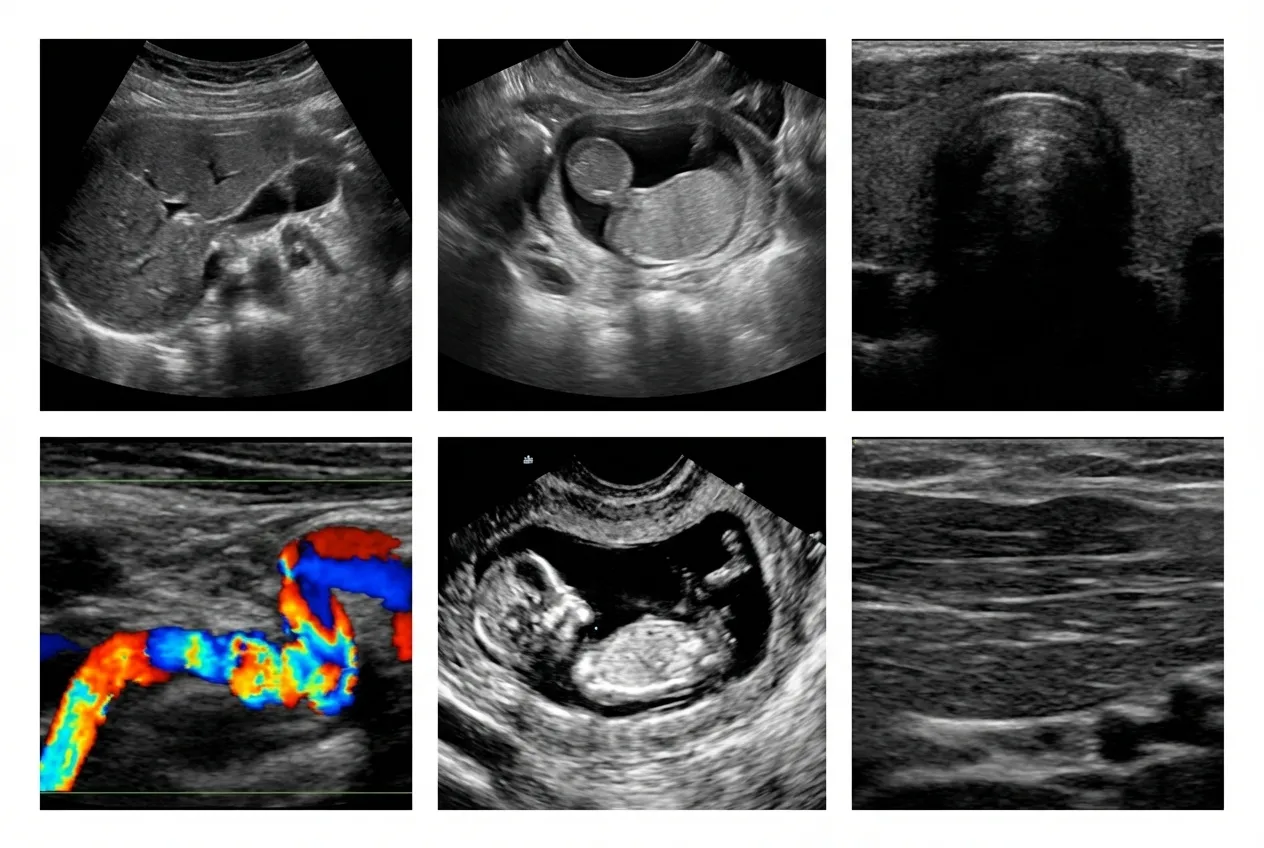

Maximum Resolution Imaging is one of the top diagnostic imaging centers in Texas, specialized in advanced MRI, and CT scanning. Our imaging machines for CT Scan, MRI and X Ray are some of the world’s most sophisticated, high-tech equipment. Our state-of-the-art imaging facility provides rapid, high-quality results with immediate and accurate diagnostics.

Medical Imaging Services We Offer

We proudly provide a wide range of imaging services catering to both corporate entities and individual clients. Our superior imaging capabilities position us as the preferred choice for healthcare providers across Texas seeking precise diagnostic imaging solutions for their patients.

From Advanced diagnostic imaging to specialized procedures, our commitment to excellence ensures that you receive the highest quality care. Explore our most in-demand services below and discover how we can assist you on your journey to optimal health and wellness.